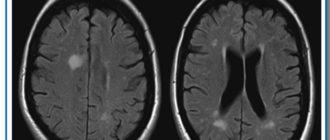

Мелкоочаговые поражения белого вещества головного мозга

Что такое очаговые изменения белого вещества головного мозга Головной мозг является центром, которой регулирует

Чем опасны очаги повышенной интенсивности

Глиоз белого вещества головного мозга: единичные и множественные очаги, признаки и прогноз жизни Заболевания